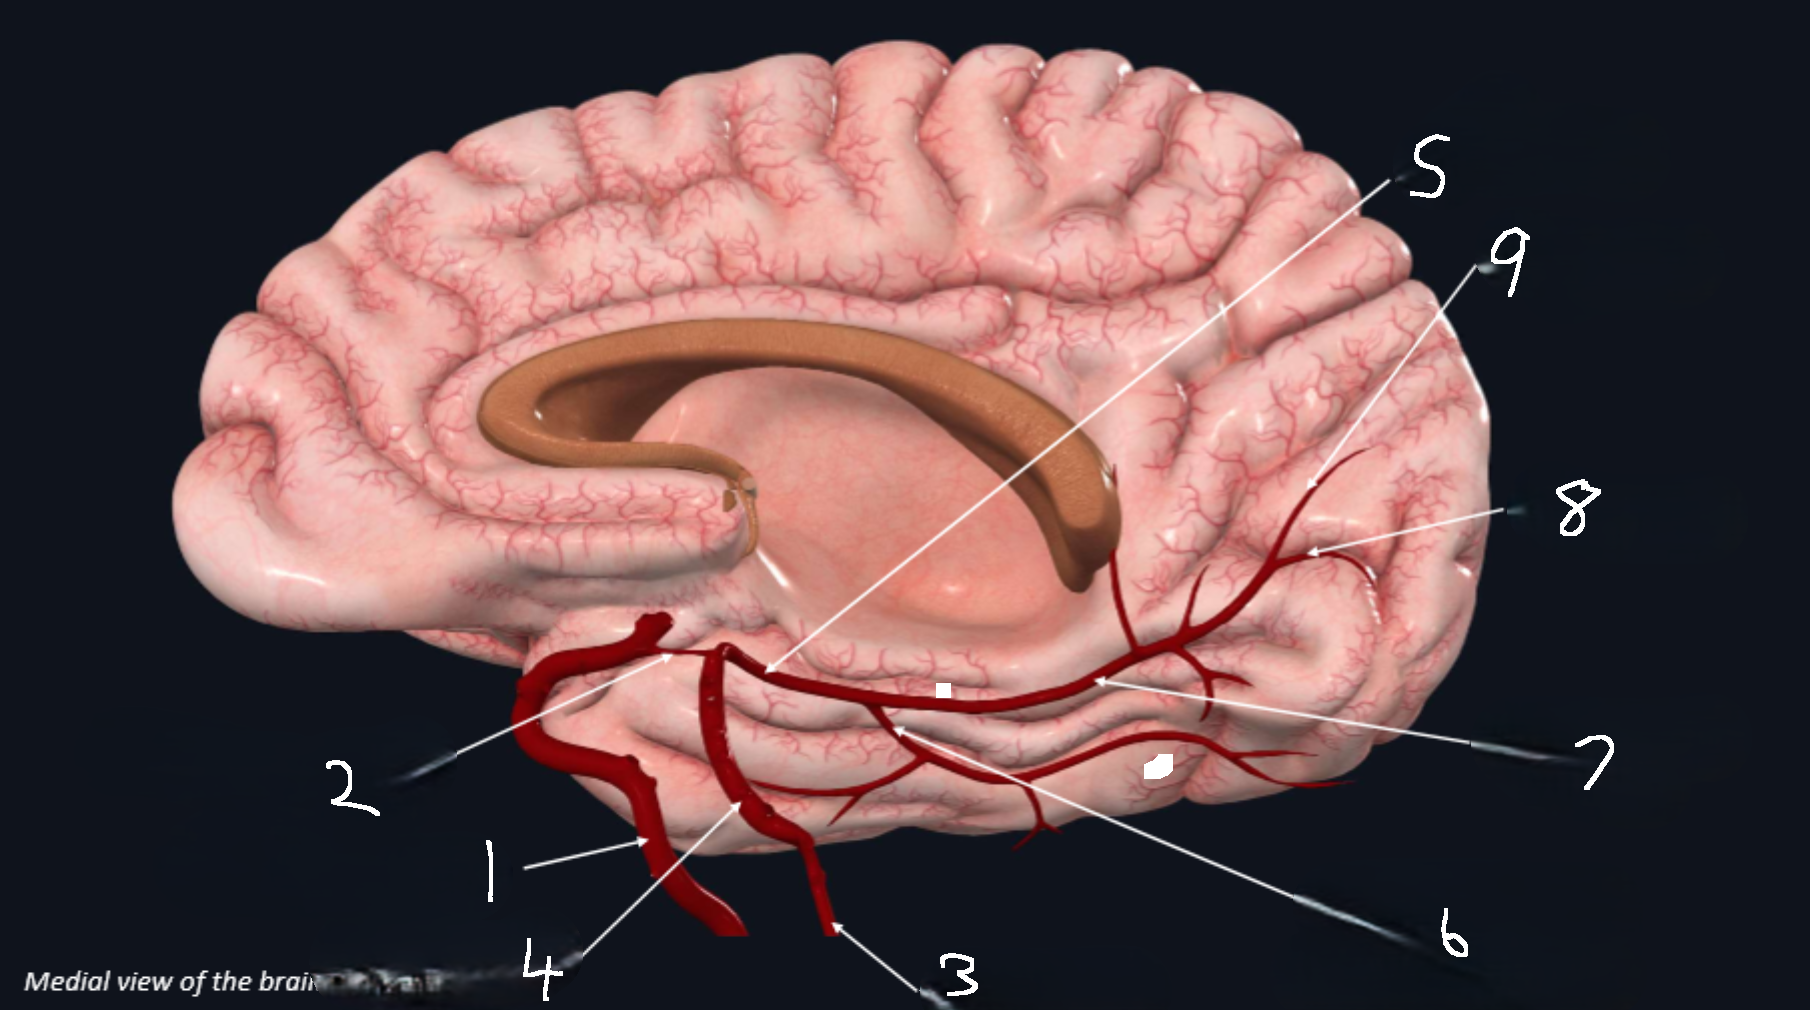

What is 1?

internal carotid artery

What is 2?

anterior cerebral artery

What is 3?

frontopolar artery

What is 4?

pericallosal artery

What is 5?

callosomarginal artery

What is 6?

corpus callosum